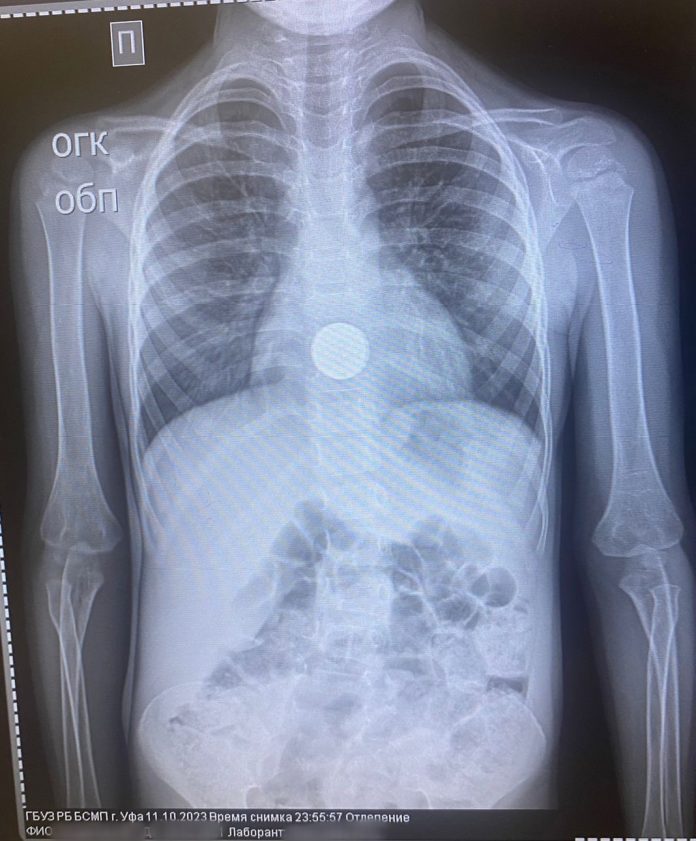

В Уфе трехлетний ребенок проглотил монету

Так, трехлетний ребенок во время игры проглотил монету. Специалисты провели гастроскопию под наркозом для извлечения монеты. Сейчас состояние ребенка удовлетворительное.